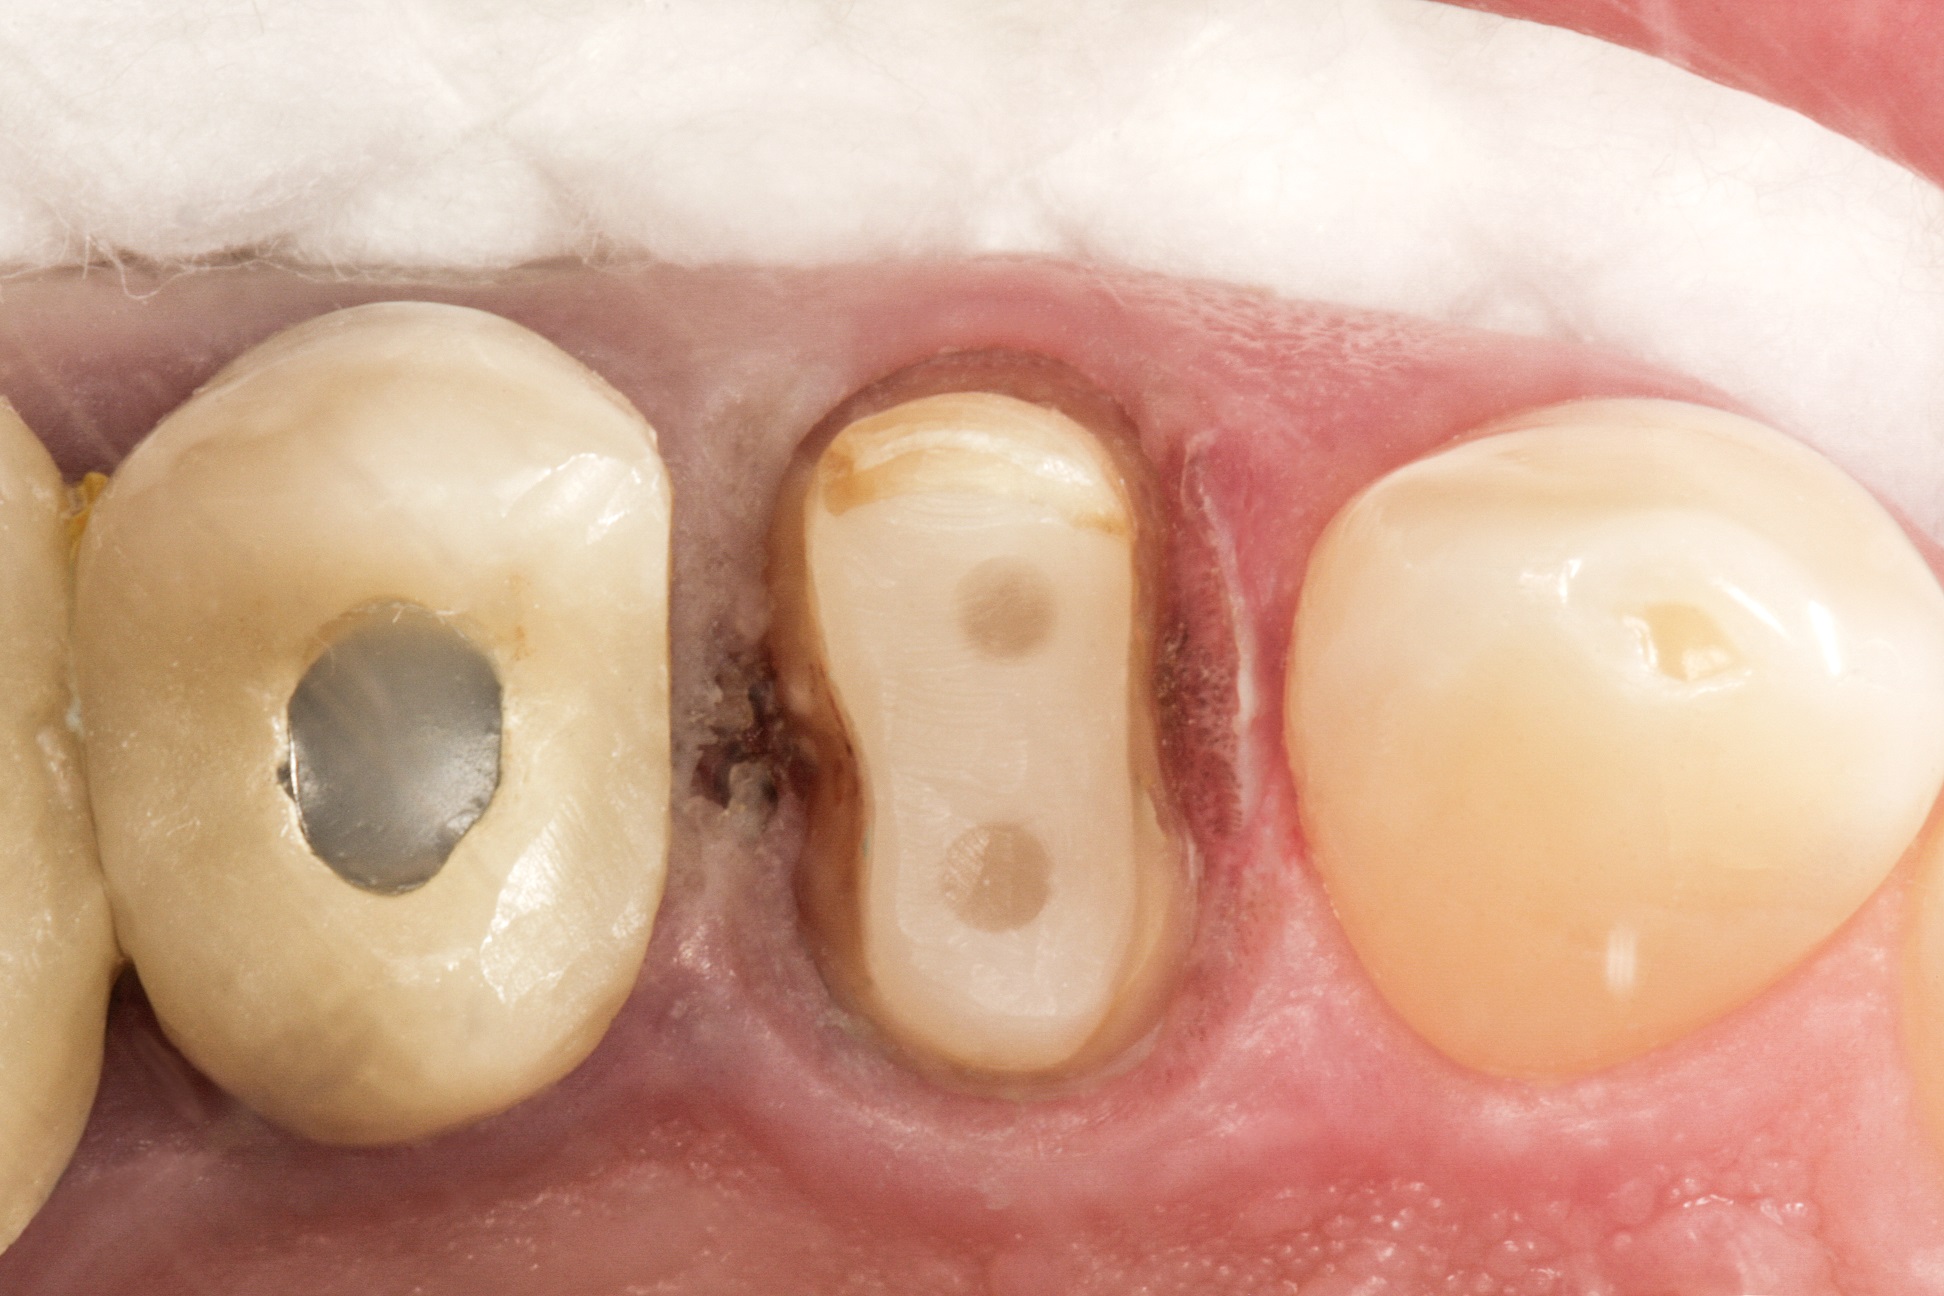

Видаляємо наявну керамічну накладку і невелику зону

каріозного ураження. Знаходимо щічний та язичний канали. За допомогою свердла

для штифтів, що є у комплекті LuxaPost, у кожному каналі створюємо ложе для

штифта глибиною 10-11 мм (рис. 2 і 3).

Фото 2. Кореневі канали після видалення матеріалу для

обтурації.

Фото 3. Робота зі свердлами LuxaPost для створення ложа для штифтів.